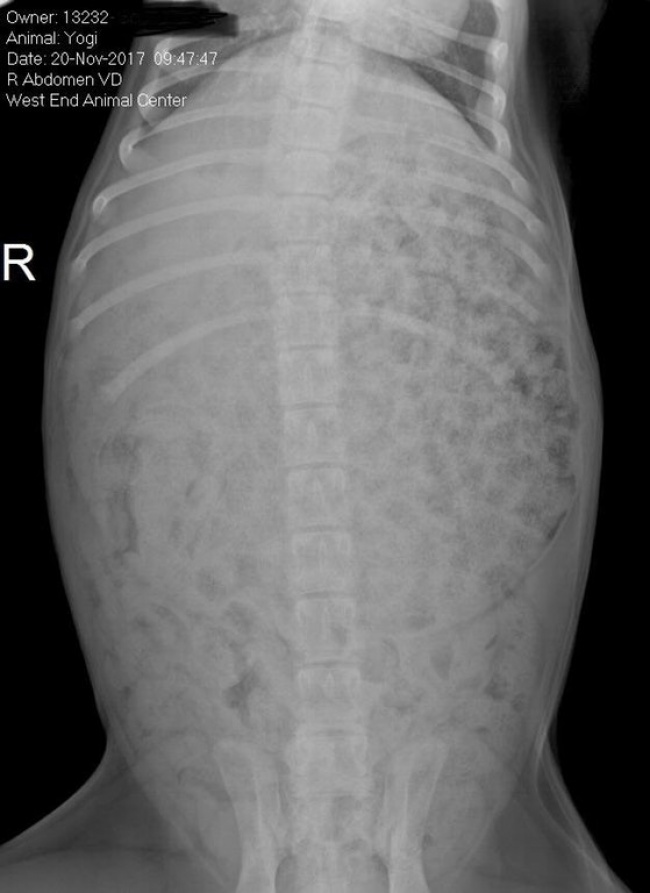

«Наш щенок лабрадора забрался в мешок с кормом прошлой ночью. $ 250 спустя я получил этот рентгеновский снимок: ни одного органа, сплошной желудок»